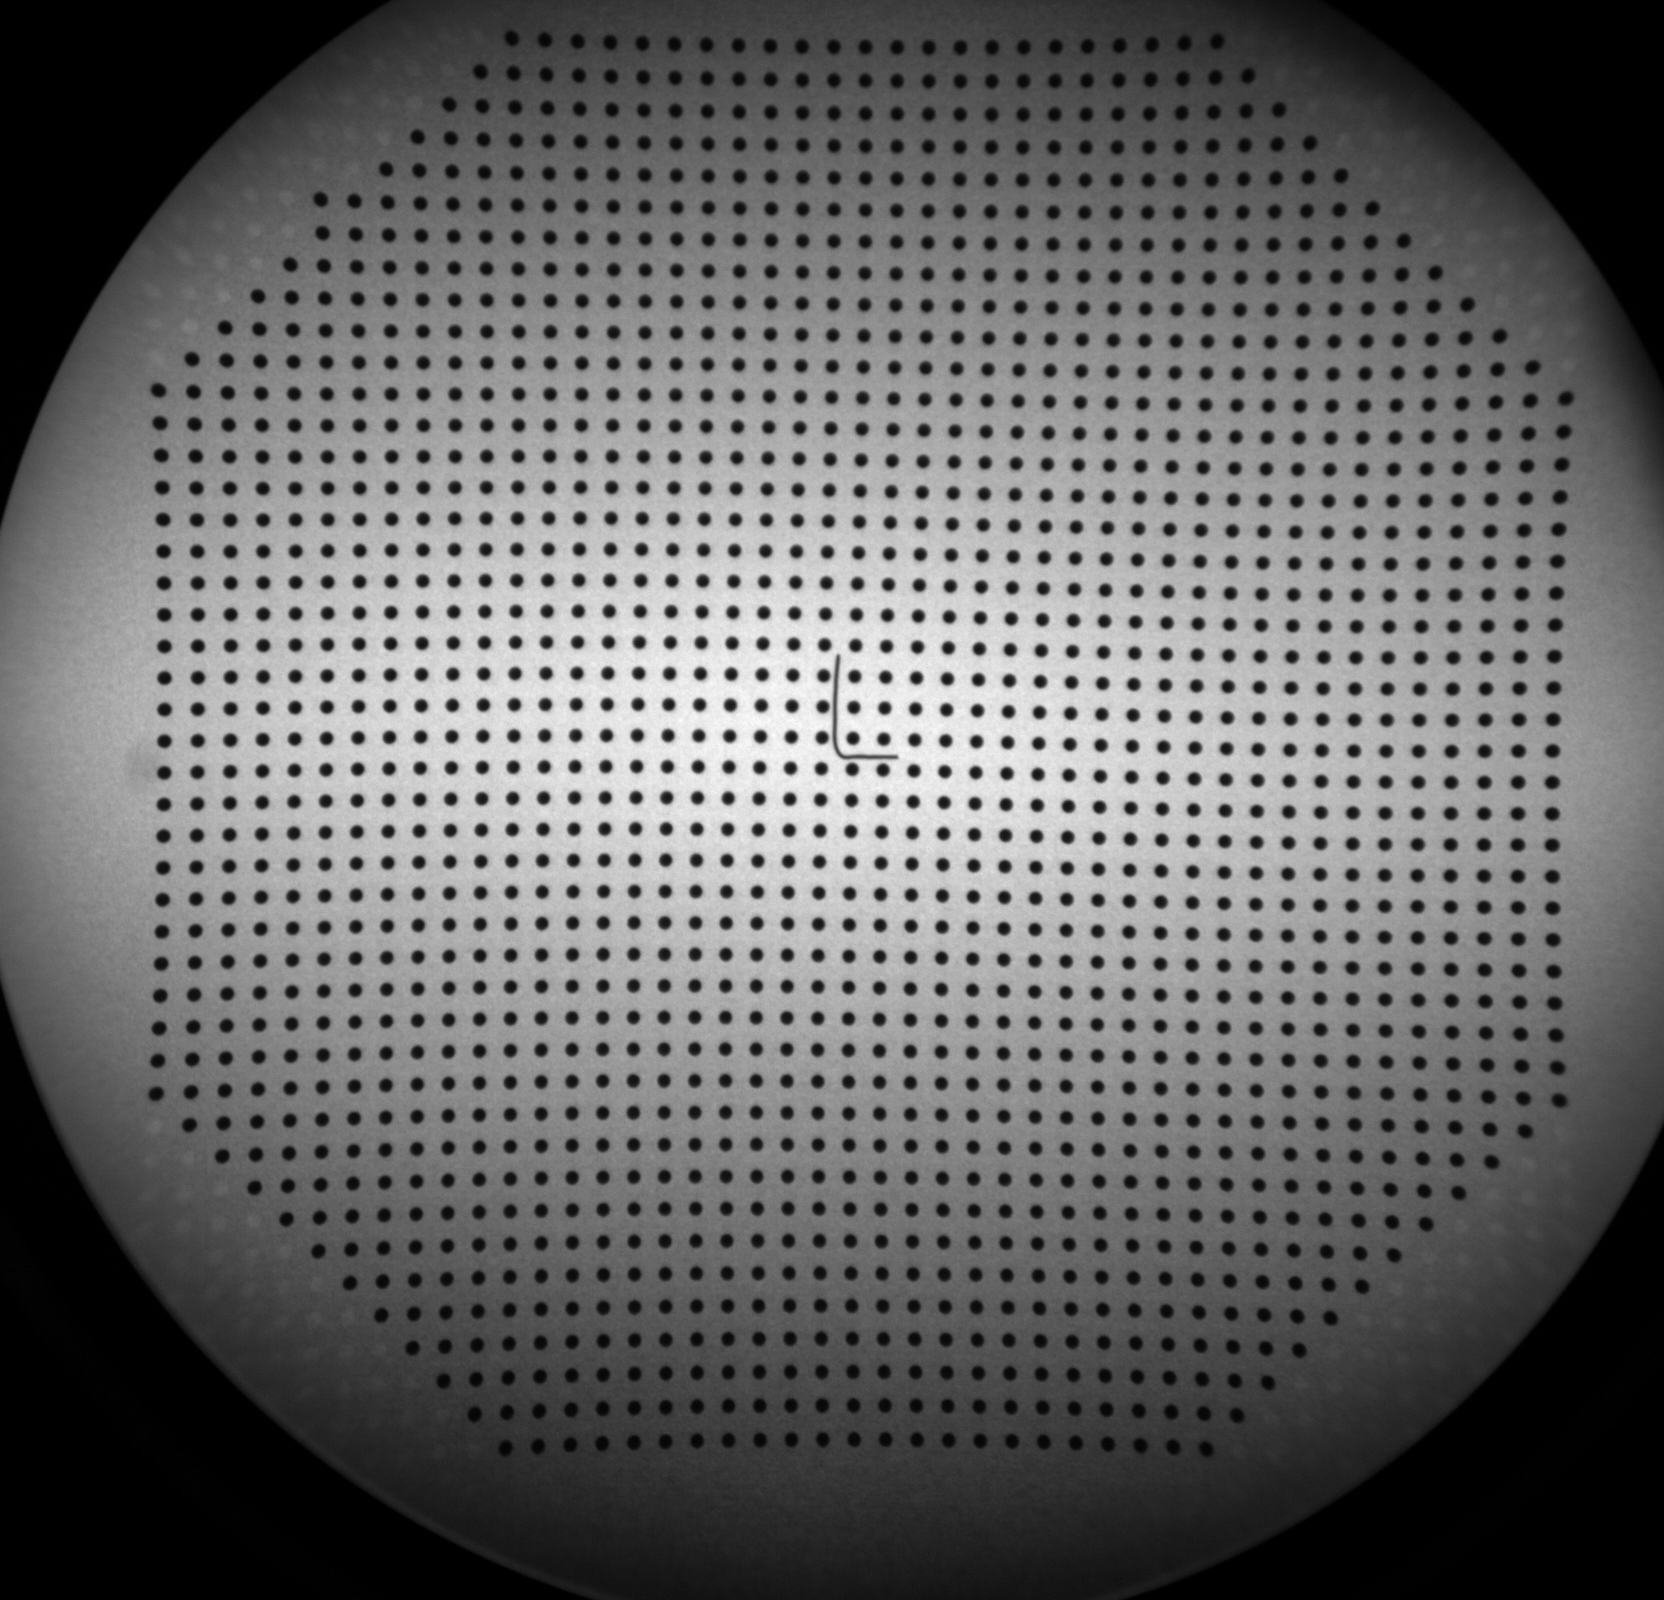

For distortion correction, a bead grid phantom (45 × 45 beads with 7 mm spacing) was affixed to the intensifier surface (Fig. 2(a)). The known geometry of the bead grid enabled precise distortion correction using a coherent point drift method to establish correspondences, followed by third-order polynomial fitting with Powell optimisation to compute the transformation.

All resulting DISCAL and SICAL values, as well as the raw distortion grid images (Fig.4(a)&4(b)), phantom measurements, and precomputed correction functions, were stored and are available within the Veriserum database. The database also includes code for computing and applying DISCAL and SICAL functions. While precomputed calibration values are available in the database for immediate application, users are welcome to reprocess the calibration parameters if necessary.

(a) DISCAL grid - Camera A